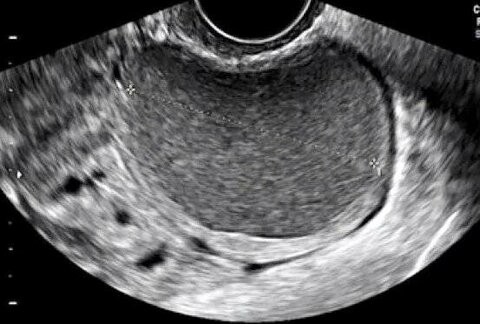

Сходила на узи после первых месячных после визанны и расстроилась . . .слева киста… откуда??? У меня никогда не было кист… после ов

На узи у меня обнаружили эндометриоидную кисту размером 21х22 мм (ранее после приема визанны она была 11х9 мм), т .е . за два месяца она выросла в два раза .

Я после начала приема Визанны уже 2 раза ходила на узи (с перерывом между узи 1,5 месяца), и когда я узистку пытала, она мне так сказала, типа гетеротропии есть, и будет понятно засохли они или нет, только после отмены через несколько месяцев, типа если не будут увеличиваться . . .

УЗИ после окончания лечения . . . Тк во время приема Визанны я делала УЗИ и справа у меня на протяжении всего приема находили то ли нелопнувший фолликул, . . .